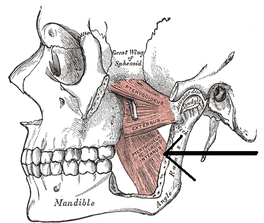

Mediale pterygoideus

De mediale pterygoideus bevindt zich aan de zijkant van...